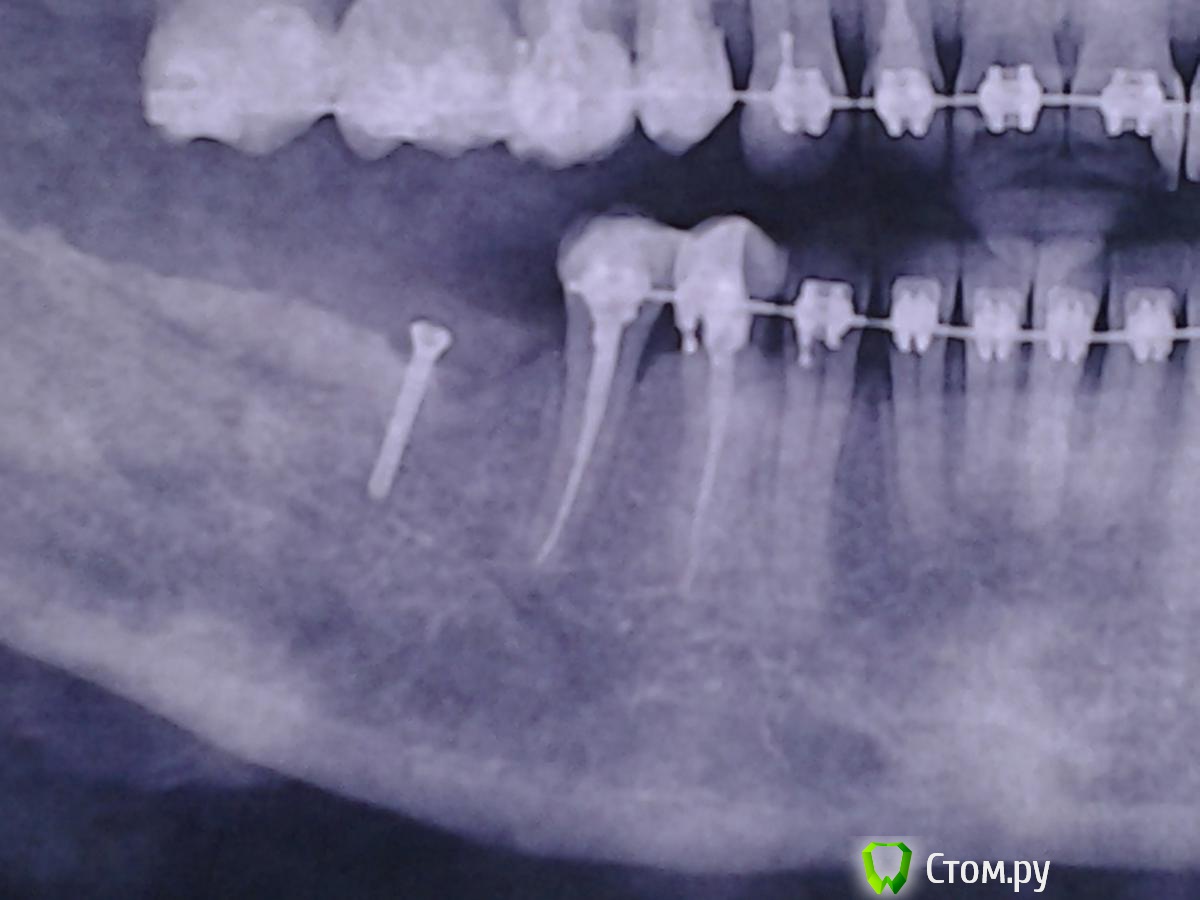

Nyurok Опубликовано 15 июня, 2014 Поделиться Опубликовано 15 июня, 2014 Здравствуйте, уважаемые врачи. С профессиональным вас праздником!Ситуация. 2 месяца назад операция "костная пластика" аутотрансплантатом. Всё хорошо, никаких субъективных ощущений. Через 1.5 месяца после операции возник сильный отек, и онемение левой половины нижней губы и левой части подбородка и практически одновременно с этим на другой стороне сделали операцию - 2 импланта и костная пластика, тоже своей костью. Принимала лекарства - кетонал, цефтриаксон, диазолин. Отек слева почти прошел, оставалась небольшая припухлость снаружи, но во рту отёк сохранялся и к тому, что было через 1 - 1.5 после операции не пришло. Справа, где импланты небольшая постоянная тупая боль. Через 2 недели от возникновения отёка (через 2 месяца после операции) в углу слева, где брали кость - открылся свищ, без заметного отделяемого, отек и онемение сохраняются. Пару дней назад справа и слева, мест забора кости, удалили некротизированные костные ткани (во время операций туда клали гемостатические губки), слева ещё удалили 1 винт из костного блока и отшлифовали верхний слой блока, зашили , место где блок. Лекарства - абактал, кетонал, диазолин.Сейчас. Справа ощущения значительно улучшились. Слева - улучшений нет. Отек, онемение, тяжесть всей левой челюсти до уха и где подчелюстные узлы.Прошу вас сказать, что есть сейчас на снимках и что делать.Состояние, как мне кажется, критическое. Надеюсь на помощь. Ссылка на комментарий

Nyurok Опубликовано 15 июня, 2014 Автор Поделиться Опубликовано 15 июня, 2014 ничего не понял, вы что снимки перевернули?Я ориентировалась где у меня право, там и снимок правой стороны. Как точно нужно - не знаю. Импланты это правая сторона, винтик левая Ссылка на комментарий

Nyurok Опубликовано 15 июня, 2014 Автор Поделиться Опубликовано 15 июня, 2014 какая зона вас смущает? обведите кружочкомизвините, не знаю как это сделать. Вся практически левая сторона нижней челюсти отличается от правой, она темнее, т.е. получается это разрежение кости? Вниз от винтика, 4-ки 5-ки до края нижней челюсти. Ведь у меня после вчерашней манипуляции нет улучшения? Значит источник инфицирования не устранен? Ссылка на комментарий